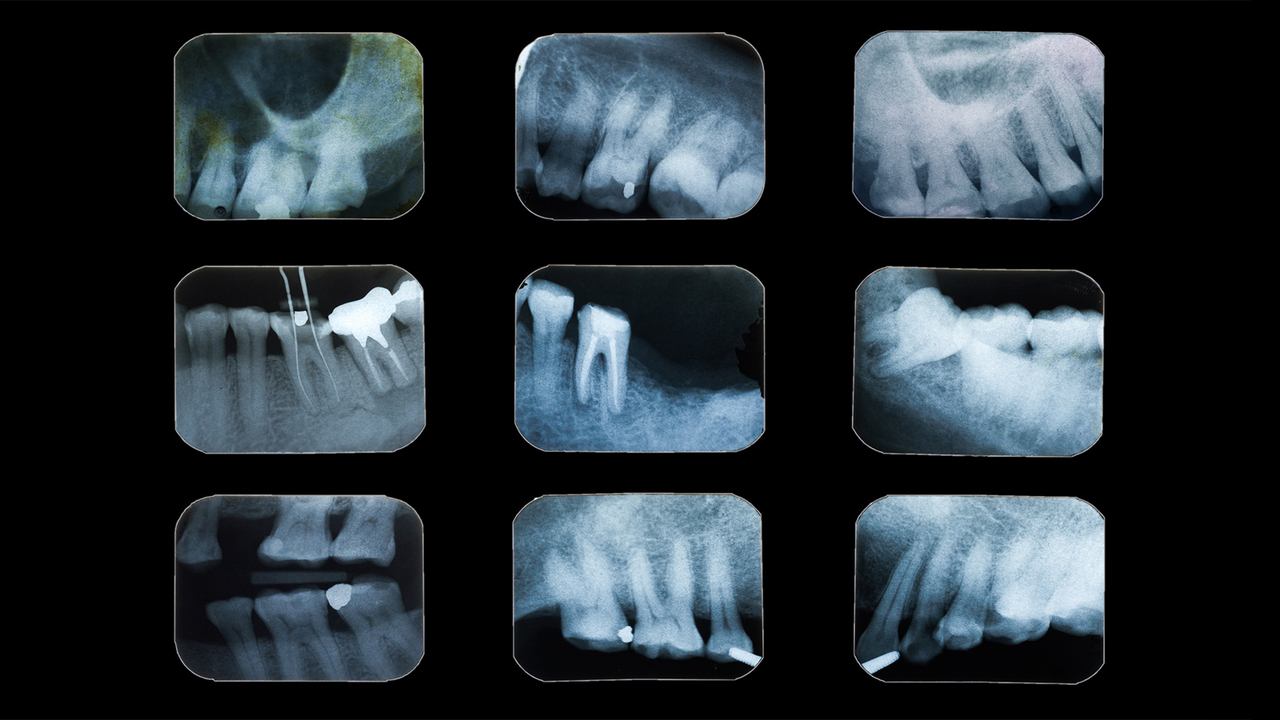

歯を削る前は、デンタルレントゲンで虫歯の窩底部(歯を削ってできた穴の底)から神経までの距離を正確に計測し、安全に進められるよう計画を立てます。

検査器具やレントゲンで、虫歯の進行度合いを調べます。